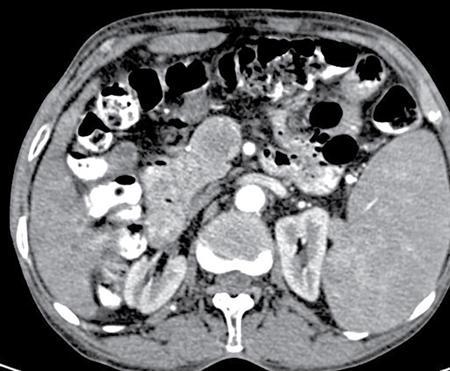

Image

Fig 7.4.5.1 Barium study of the patient.

Fig 7.4.5.2 CECT of the patient.

Fig 7.4.5.3 CECT of the patient.

Observations

Barium study shows large filling defect in the antrum forming acute angles with the wall. Undulating contour is seen along greater curvature with ulceration of overlying mucosal irregularity.

CECT shows a large lobulated mass involving lesser curvature and antrum with marked wall thickening along distal greater curvature.

Diagnosis

Carcinoma stomach.